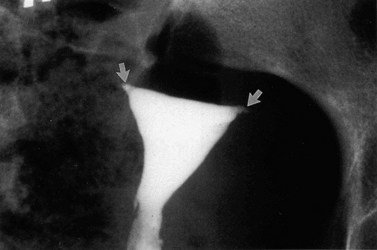

Медицинские снимки: Проходимость маточных труб

Раздел: Кадры-подсказки